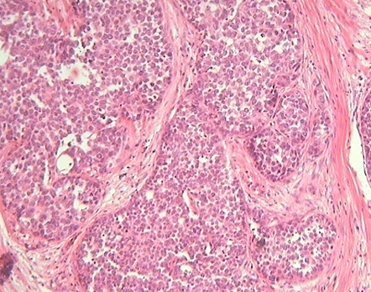

Гистологический препарат карциноида

Карциноид развивается из аргирофильных клеток кишечных крипт и относится к гормонально-активным опухолям, продуцирующим серотонин, гистамин, брадикинин и простагландины. Опухоль обычно небольшого размера (около 1,5 см), располагается в подслизистой основе, слизистая оболочка над ней не изменена. Изъязвление, стеноз и кровотечение развиваются преимущественно а стадии малигнизации. Различают пять гистологических типов карциноида. Чаще втречаются тип А - узловатая (22,6%) и тип В - трабекулярная, или лентовидная (21%) формы, реже - тип С - тубулярная с ацинарными или розеткообразными структурами (3,2%) и тип D - малодифференцированный, или типичный (9,2%). Примерно в половине случаев (43,5%) наблюдаются смешанные формы. Аргентаффинный карциноид принадлежит преимущественно к типу, аргирофильный - к смешанному типу. Неактивные формы карциноида наблюдаются при типе В и смешанном типе. Все карциноиды являются потенциально злокачественными. Риск малигнизации растет по мере увеличения размеров опухоли. Карциноид содержит большое количество серотонина при высокой активности допадекарбоксилазы и низкой активности аминооксидазы. В сыворотке рови значительно повышается содержание серотонина, а в моче - продукта аспада серотонина (5-оксииндолуксусная кислота). Образующийся в опухолевой ткани серотонин расширяет капилляры, вызывая отек и бронхоспазм. Печень, пораженная метастазами опухоли, содержит повышенное количество калликреина - фермента, с помощью которого из кининогена плазмы крови образуется брадикинин, обладающий способностью расширять сосуды, вызывать приливы, спазмы бронхов и кишечника. Приливы вызывают также катехоламины, которые способствуют высвобождению калликреина.